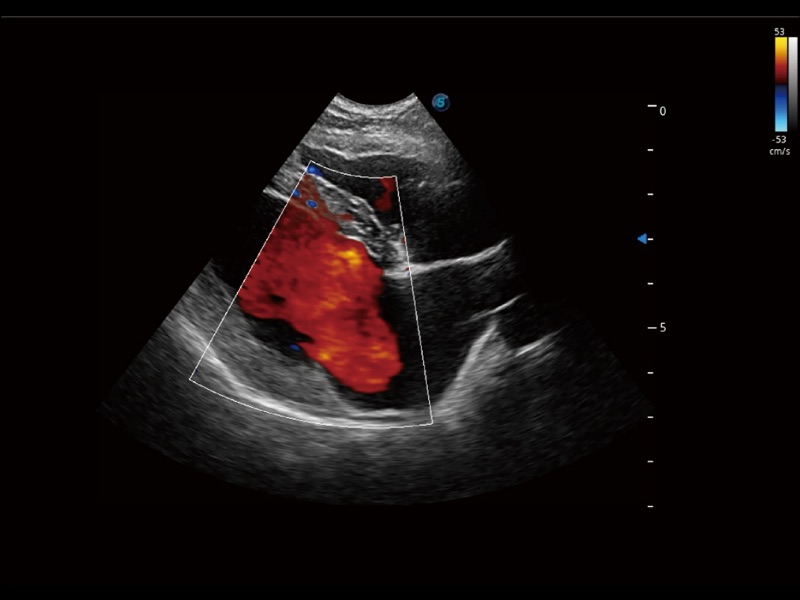

优异的基础图像

(犬)肾脏显微血流

(犬)髂动脉血流